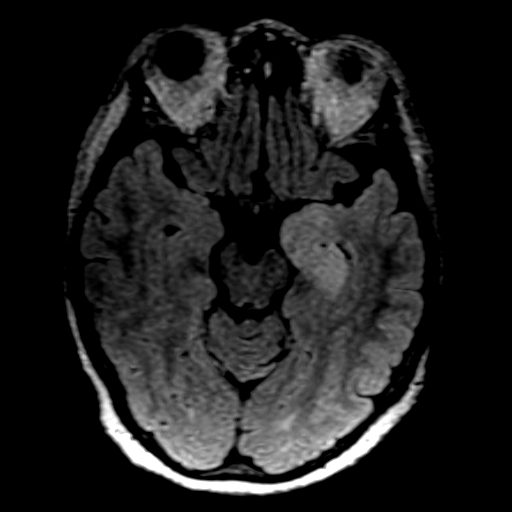

Viral Encephalitis – MRI